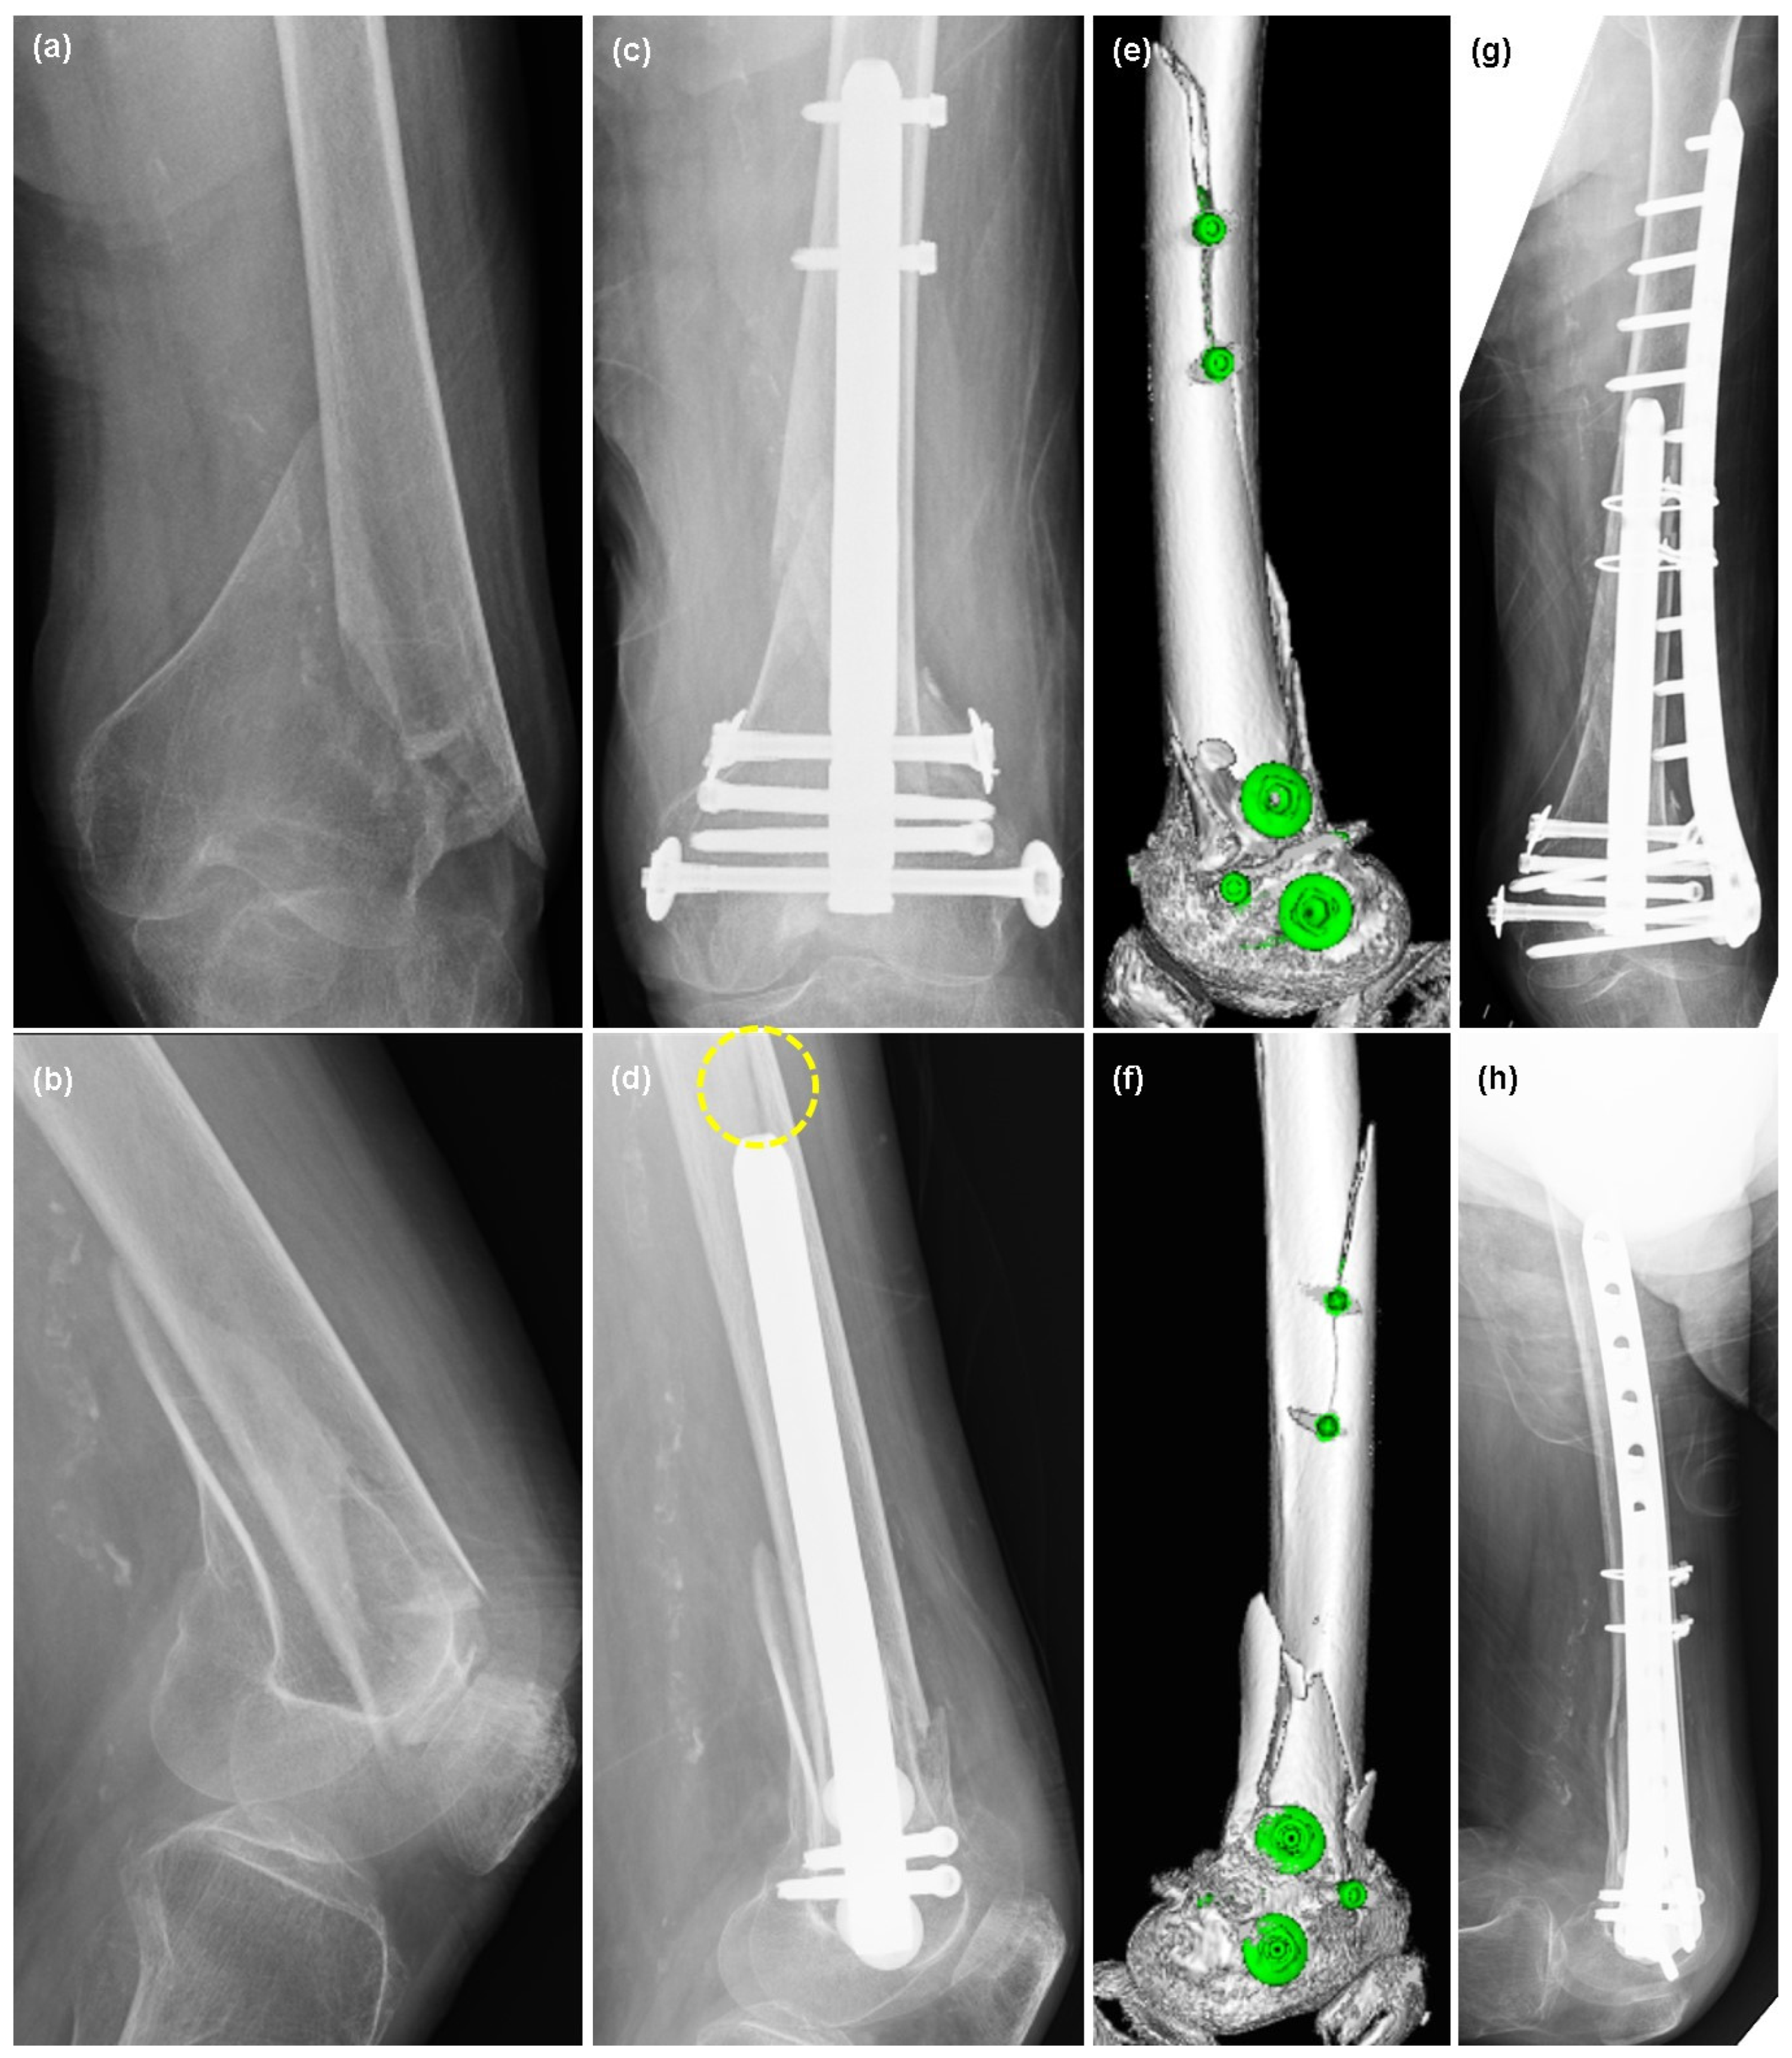

2.1. Patient 1